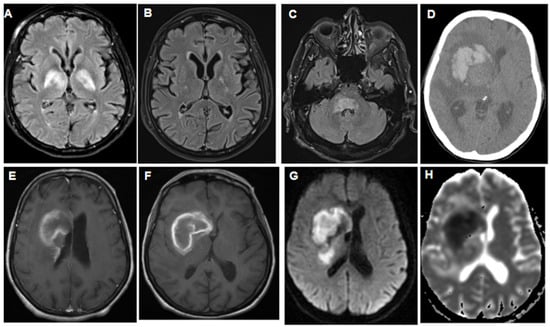

Most patients displayed lobar lesions in MRI (24 cases, Figure 2), while other locations included the cerebellum (6), hypophysis (2), ocular bulb (2), hypothalamus (1), intraventricular (1), basal ganglia (8), leptomeninges (1), and periventricular regions (8). Notably, seven patients had brainstem lymphoma, and three exhibited IVL, all showing a stroke-like appearance in MRI scans.

Among the PCNSL patients, 11 had a primary infiltrating appearance, 8 showed ring-enhancing lesions, and 5 had hemorrhagic involvement, Figure 3. Histopathological examination revealed that 42 patients had findings consistent with DLBCL, with 1 case each of Burkitt-like lymphoma and non-differentiated lymphoma.

Figure 2. A series of imaging findings of patients with PCNSL and various neurological symptoms, demonstrating initial presentation, treatment response, and follow-up imaging, providing insights into the diagnostic process and radiographic treatment outcomes. (A): T2-flair MRI with gadolinium of a 79-year-old patient presenting with ataxia and episodes of delirium, showing bi-thalamic hyperintensity. (B): T2-flair MRI with gadolinium of the same patient after treatment, demonstrating evidence of near-complete resolution. (C): T2-flair MRI with gadolinium of a 64-year-old patient presenting with 6 months of ataxia and dizziness. (D): A CT scan of a 64-year-old patient with left hemi-syndrome, initially presenting as a hemorrhage. (E,F): T1+gadolinium MRI scan of the same patient exhibiting the same hemorrhage with contrast enhancement, as well as small periventricular gadolinium enhancement that was not visible in the earlier CT scan. (G): Diffusion-weighted imaging (DWI) of the hemorrhagic lesion, confirming the diagnosis of hemorrhagic stroke. (H): ADC (apparent diffusion coefficient) MRI series of the same patient, providing additional information about the hemorrhagic stroke.